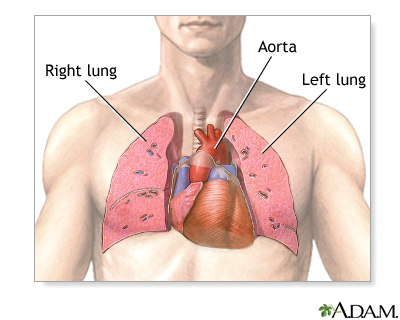

The right side of the heart pumps blood into the pulmonary artery and then through the lungs, where it picks up oxygen. Blood returns to the left side of the heart, where it is pumped to the rest of the body.

Heart-lung transplant - series - Normal anatomy

Presentation